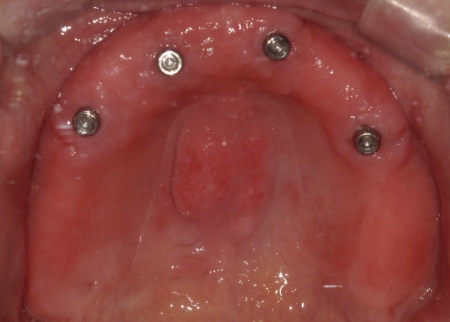

傷が治り、インプラントが顎の骨にしっかりと結合したことを確認したら、インプラントの頭部分に入れ歯と連結するための部分となる「アタッチメント」を装着しました。

次に、上顎には「インプラント支持型義歯(インプラントオーバーデンチャー)」を金属床義歯で作製します。

金属床にすることで、従来の樹脂製義歯と比べて薄く作ることが可能になり、装着による違和感の軽減が見込めます。